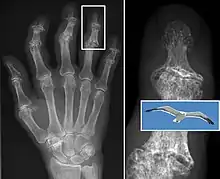

In smaller joints, such as at the fingers, hard bony enlargements, called Heberden's nodes (on the distal interphalangeal joints) or Bouchard's nodes (on the proximal interphalangeal joints), may form, and though they are not necessarily painful, they do limit the movement of the fingers significantly. Osteoarthritis of the toes may be a factor causing formation of bunions,[16] rendering them red or swollen.

In 1990, the American College of Rheumatology, using data from a multi-center study, developed a set of criteria for the diagnosis of hand osteoarthritis based on hard tissue enlargement and swelling of certain joints.[55] These criteria were found to be 92% sensitive and 98% specific for hand osteoarthritis versus other entities such as rheumatoid arthritis and spondyloarthropathies.[56]

Bone (left) and clinical (right) changes of the hand in osteoarthritis